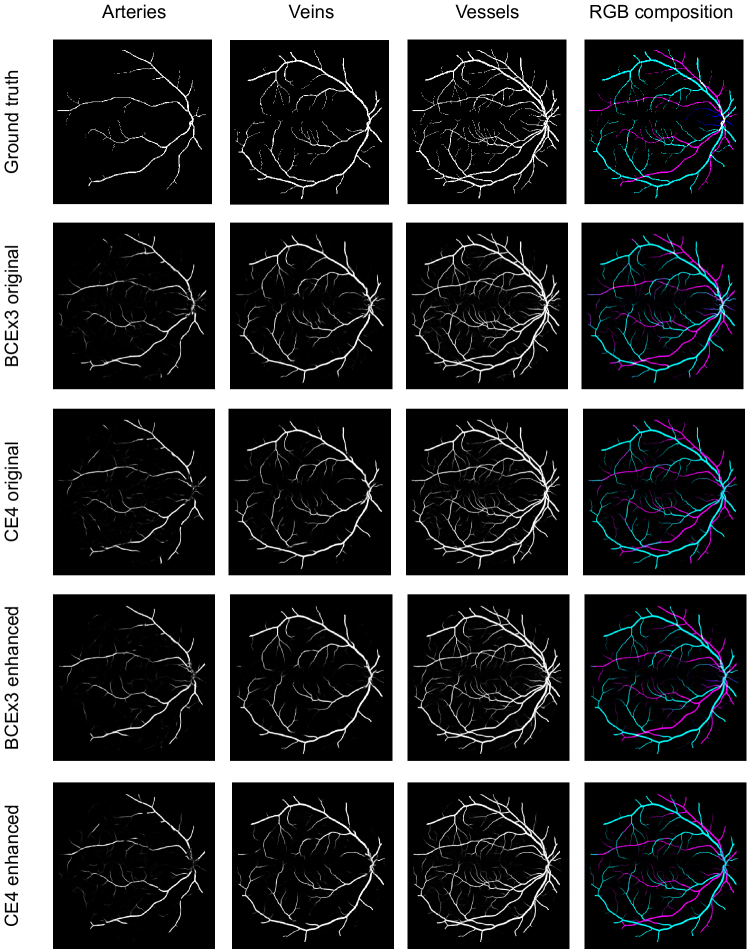

Lastly, Figure 13 shows representative examples of the predicted probability maps that were obtained by the trained models using both losses and the enhanced retinographies as input. In each case, the figure depicts the RGB composition of the predicted maps for a better clarity.

In addition to the higher segmentation performance using BCE3, crossings are handled in a more intuitive way. In this case, crossing pixels are simply assigned to both artery and vein classes at a time and the network is able to detect them (see PR curve depicted in Figure 11) while allowing to achieve a continuous segmentation of both the arterial and venular trees. For CE4, differently, the crossings are mostly treated as a separate class (along with the uncertain vessels), either to detect them [39], or to let the network detect the artery or the vein above the other [36, 37, 40, 41]. There is also some approach in which the crossings belong to the same class as that of the upper vessel [38]. Nevertheless, whichever of these alternatives gives raise to incomplete segmentation maps for both arteries and veins. Multiple examples of this effect can be found in Figure 14. Taking all this into account, it can be stated that the MS strategy favors a better segmentation of the different structures, and handles the different cases in a much simpler way.

Another relevant point that can be observed in the different figures is the beneficial effect of the preprocessing for the A/V classification. As can be seen in Table 3 and Figure 12, the performance of the networks is, in general, better when they are trained using the enhanced images than when they are trained using the original ones. In fact, this improvement can be clearly appreciated in Figure 13, which depicts the probability maps that were predicted by the networks for a RITE-test retinography. When comparing the predictions of the “enhanced” and the “original” alternatives, it can be observed that some manifest classification errors disappear, an thus the arteries and veins continuity is slightly better preserved. Regarding the vessels segmentation, in light of the results, the preprocessing does not lead to such a significant improvement in the networks performance.